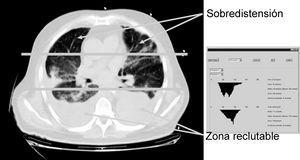

Otro parámetro ventilatorio estudiado es el empleo de un flujo decelerado en lugar de un patrón de flujo constante, asociándose con él una reducción de los fenómenos de sobredistensión pulmonar en las zonas no dependientes, así recientemente Prella et al39 en un diseño experimental en el que miden el grado de aireación pulmonar mediante estudios con tomografía axial computarizada (TAC), demuestran uno de los mecanismos por los que puede ser ventajoso el empleo de la ventilación controlada por presión o con flujo decelerado sobre la ventilación de flujo constante, este mecanismo consiste en una mejor distribución del gas en el pulmón, mediada por un discreto efecto de reclutamiento de zonas pulmonares dañadas, pero sobre todo por evitar fenómenos de sobredistensión en zonas apicales pulmonares, sin que se produzca ningún cambio en la presión alveolar, ni en el intercambio gaseoso (fig. 6).

Figura 6. Detección de zonas de compromiso mecánico mediante tomografía axial computarizada (TAC). El empleo de nueva tecnología de radiología y análisis de las imágenes (creación de histogramas de densidades) nos permite analizar zonas del pulmón que podrían participar en la producción de lesión pulmonar inducida por el respirador (VILI).